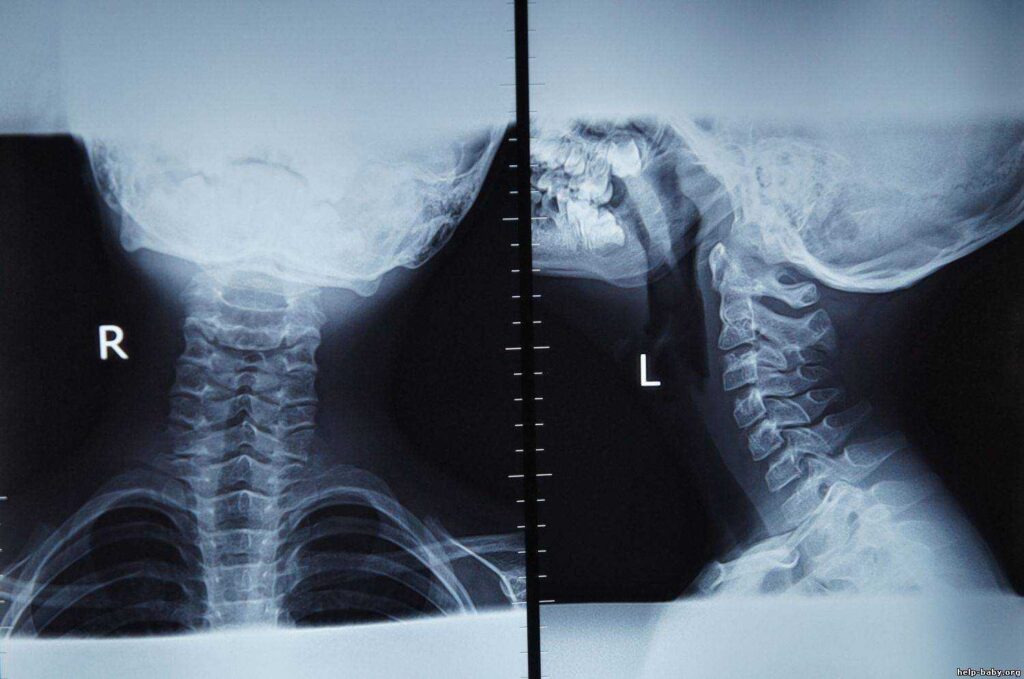

Медицинские снимки: рентген позвоночника сбоку